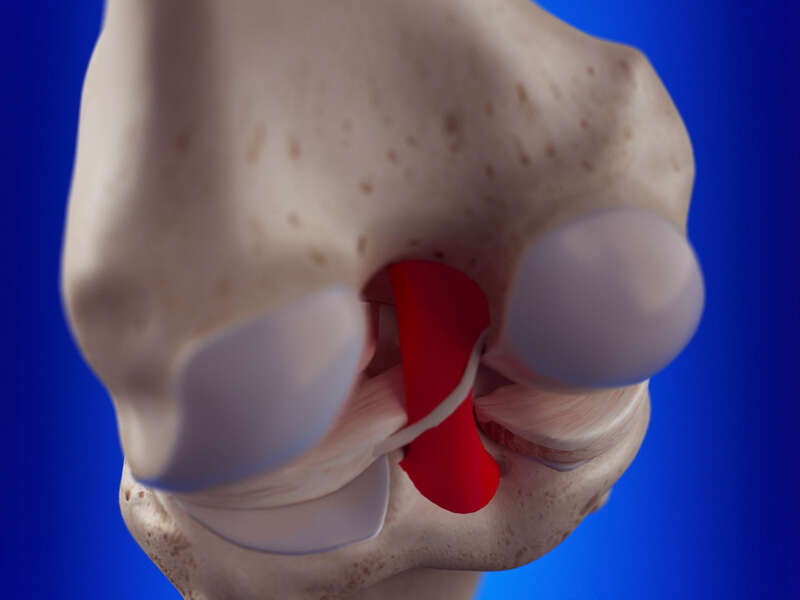

Les ligaments croisés sur des tissus fibro-élastique très solides, insérés entre le tibia et le fémur à l’intérieur de l’articulation du genou dans l’échancrure inter-condylienne. On en compte deux, un antérieur et un postérieur et forme ce que l’on appelle le pivot central.

Le ligament croisé antérieur (LCA) s’insère à la partie antéro-interne du tibia et sur la face interne du condyle fémoral externe. Le ligament croisé postérieur (LCP) est tendu entre la partie postéro-externe du tibia et sur la face externe du condyle fémoral interne.

Ils jouent un rôle de stabilisateur du genou dans les mouvements de torsion et de translation (ou tiroir) antérieur et postérieur.